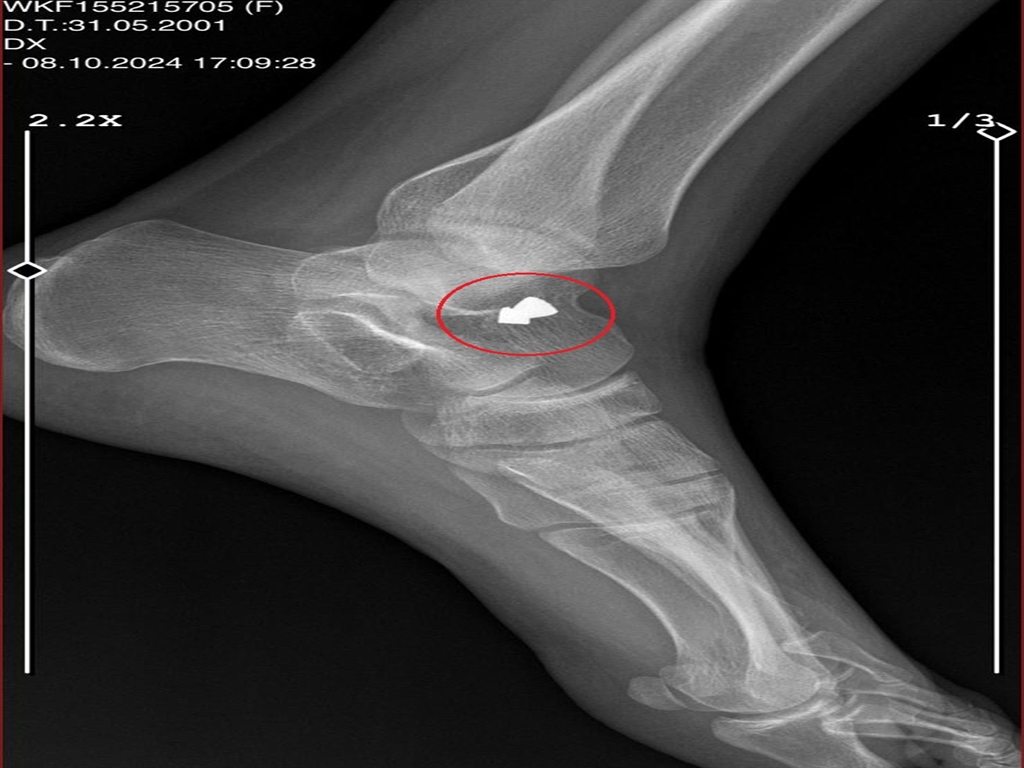

Bursa'da sevgilisi A.K.'nin (32) havalı tüfekle vurup, yaklaşık 1 ay alıkoyduğu Ayşe Ç. (23), vurulduktan 4 gün sonra hastaneye götürüldüğünü, ayağında saçma kaldığını röntgen ile fark ettiğini, buna rağmen bir daha tedavi görmediğini söyledi. A.K.'den şikayetçi olup, uzaklaştırma kararı aldıran Ayşe Ç., "Buna rağmen bana tehdit mesajları atıyor. Ölmek istemiyorum. Bir kadın cinayetine kurban gitmek istemiyorum" dedi.

A.K.'nin olaydan 4 gün sonra kendisini doktora götürdüğünü söyleyen Ayşe Ç., "O kadar çok baskı yaptı ki hastanede bile şikayetçi olamadım. Doktorun yanındayken bile gözlerimle temas kuruyordu. Korkmuştum. Zaten doktora da ayağımı kapıya vurduğumu söyledim. Ayak kemiğim çatlamış, alçıya bu yüzden aldılar. Eve geldiğimde e-Nabız uygulamasından röntgenime baktığımda, saçmanın ayağımın içinde kaldığını gördüm; ama beni bir daha hastaneye götürmedi" diye konuştu.'EVE GETİRDİĞİ KIZ, KAÇMAMA YARDIMCI OLDU'

Yalova'ya döndükten sonra, 19 Ekim'de sol kemiğine isabet eden saçmanın ameliyat ile çıkarıldığını söyleyen Ayşe Ç., "Evden kaçabilmem için bir imkan yoktu. A.K., en son gün, evden gitmeden önce beni darbetti. Saçlarımdan tutarak, yerde ayakkabılarıyla tekmeledi. Sonra evden gitti. Ardından başıma diktiği adam uyuyakaldı. Bana yardımcı olması için eve getirdiği kız, kaçmama yardımcı oldu. Valizime kıyafetlerimi topladım. Evden kaçtım" dedi.'1 AY AYAĞIMDA SAÇMAYLA GEZDİM'

A.K.'nin kendisini tehdit ettiğini Ayşe Ç. "Uzaklaştırma kararı aldırdım. Buna rağmen bana tehdit mesajları atıyor. Benim can güvenliğim yok. Ölmek istemiyorum. Bir kadın cinayetine kurban gitmek istemiyorum. Bu konuyla ilgili gerekenin yapılmasını bekliyorum. Taşınıp gitsem de bu şahıs peşimizi bırakmayacak. Yolda yürürken bile, bakkala çıktığımda bile korkarak çıkıyorum. Biri yanımdan geçtiğinde korkuyorum. 1 ay ayağımda saçmayla gezdim. Ailemin yanına geldiğimde korkudan söyleyemedim. Arkadaşıma konuyu anlattığımda, o beni hastaneye götürdü. Daha yeni ameliyat oldum. Saçmayı çıkarttılar, şu an dikişli ayağım. Bu insan, bende kalıcı bir hasar bıraktı" diye konuştu.